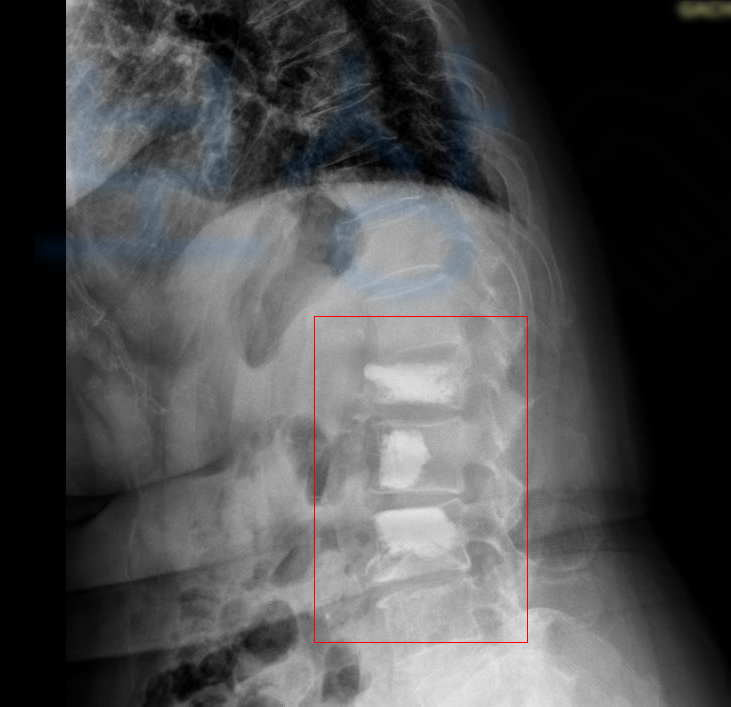

의료용 시멘트를 주입하는 시술입니다. 전문 용어로는 **경피적 척추 성형술 ** Vertebroplasty이라고도 부르며 피부를 절개하는 등의 수술이 아니기에 경피적 (바늘이 피부를 통과하는) 시술입니다.

허리에 극심한 통증이 몰려와 근처 허리 전문 병원에 내원하여 정밀검사를 받으셨고 그 결과 요추 1번의 압박골절 진단받았습니다.

골밀도가 좋지 않아 향후 골절된 척추체가 더 무너질 가능성이 있어 박@@님은 허리 시멘트시술 즉 경피적 척추성형술 (VP 시술)을 받았고 허리 통증은 점점 호전되는 것 같았죠.

보상 과정과 가능성을 설명해드렸습니다. 이후 허리 시멘트시술 실시한 요추 1번 골절의 후유장해 보험금 청구를 위임받아 진행하게 되었는데요,